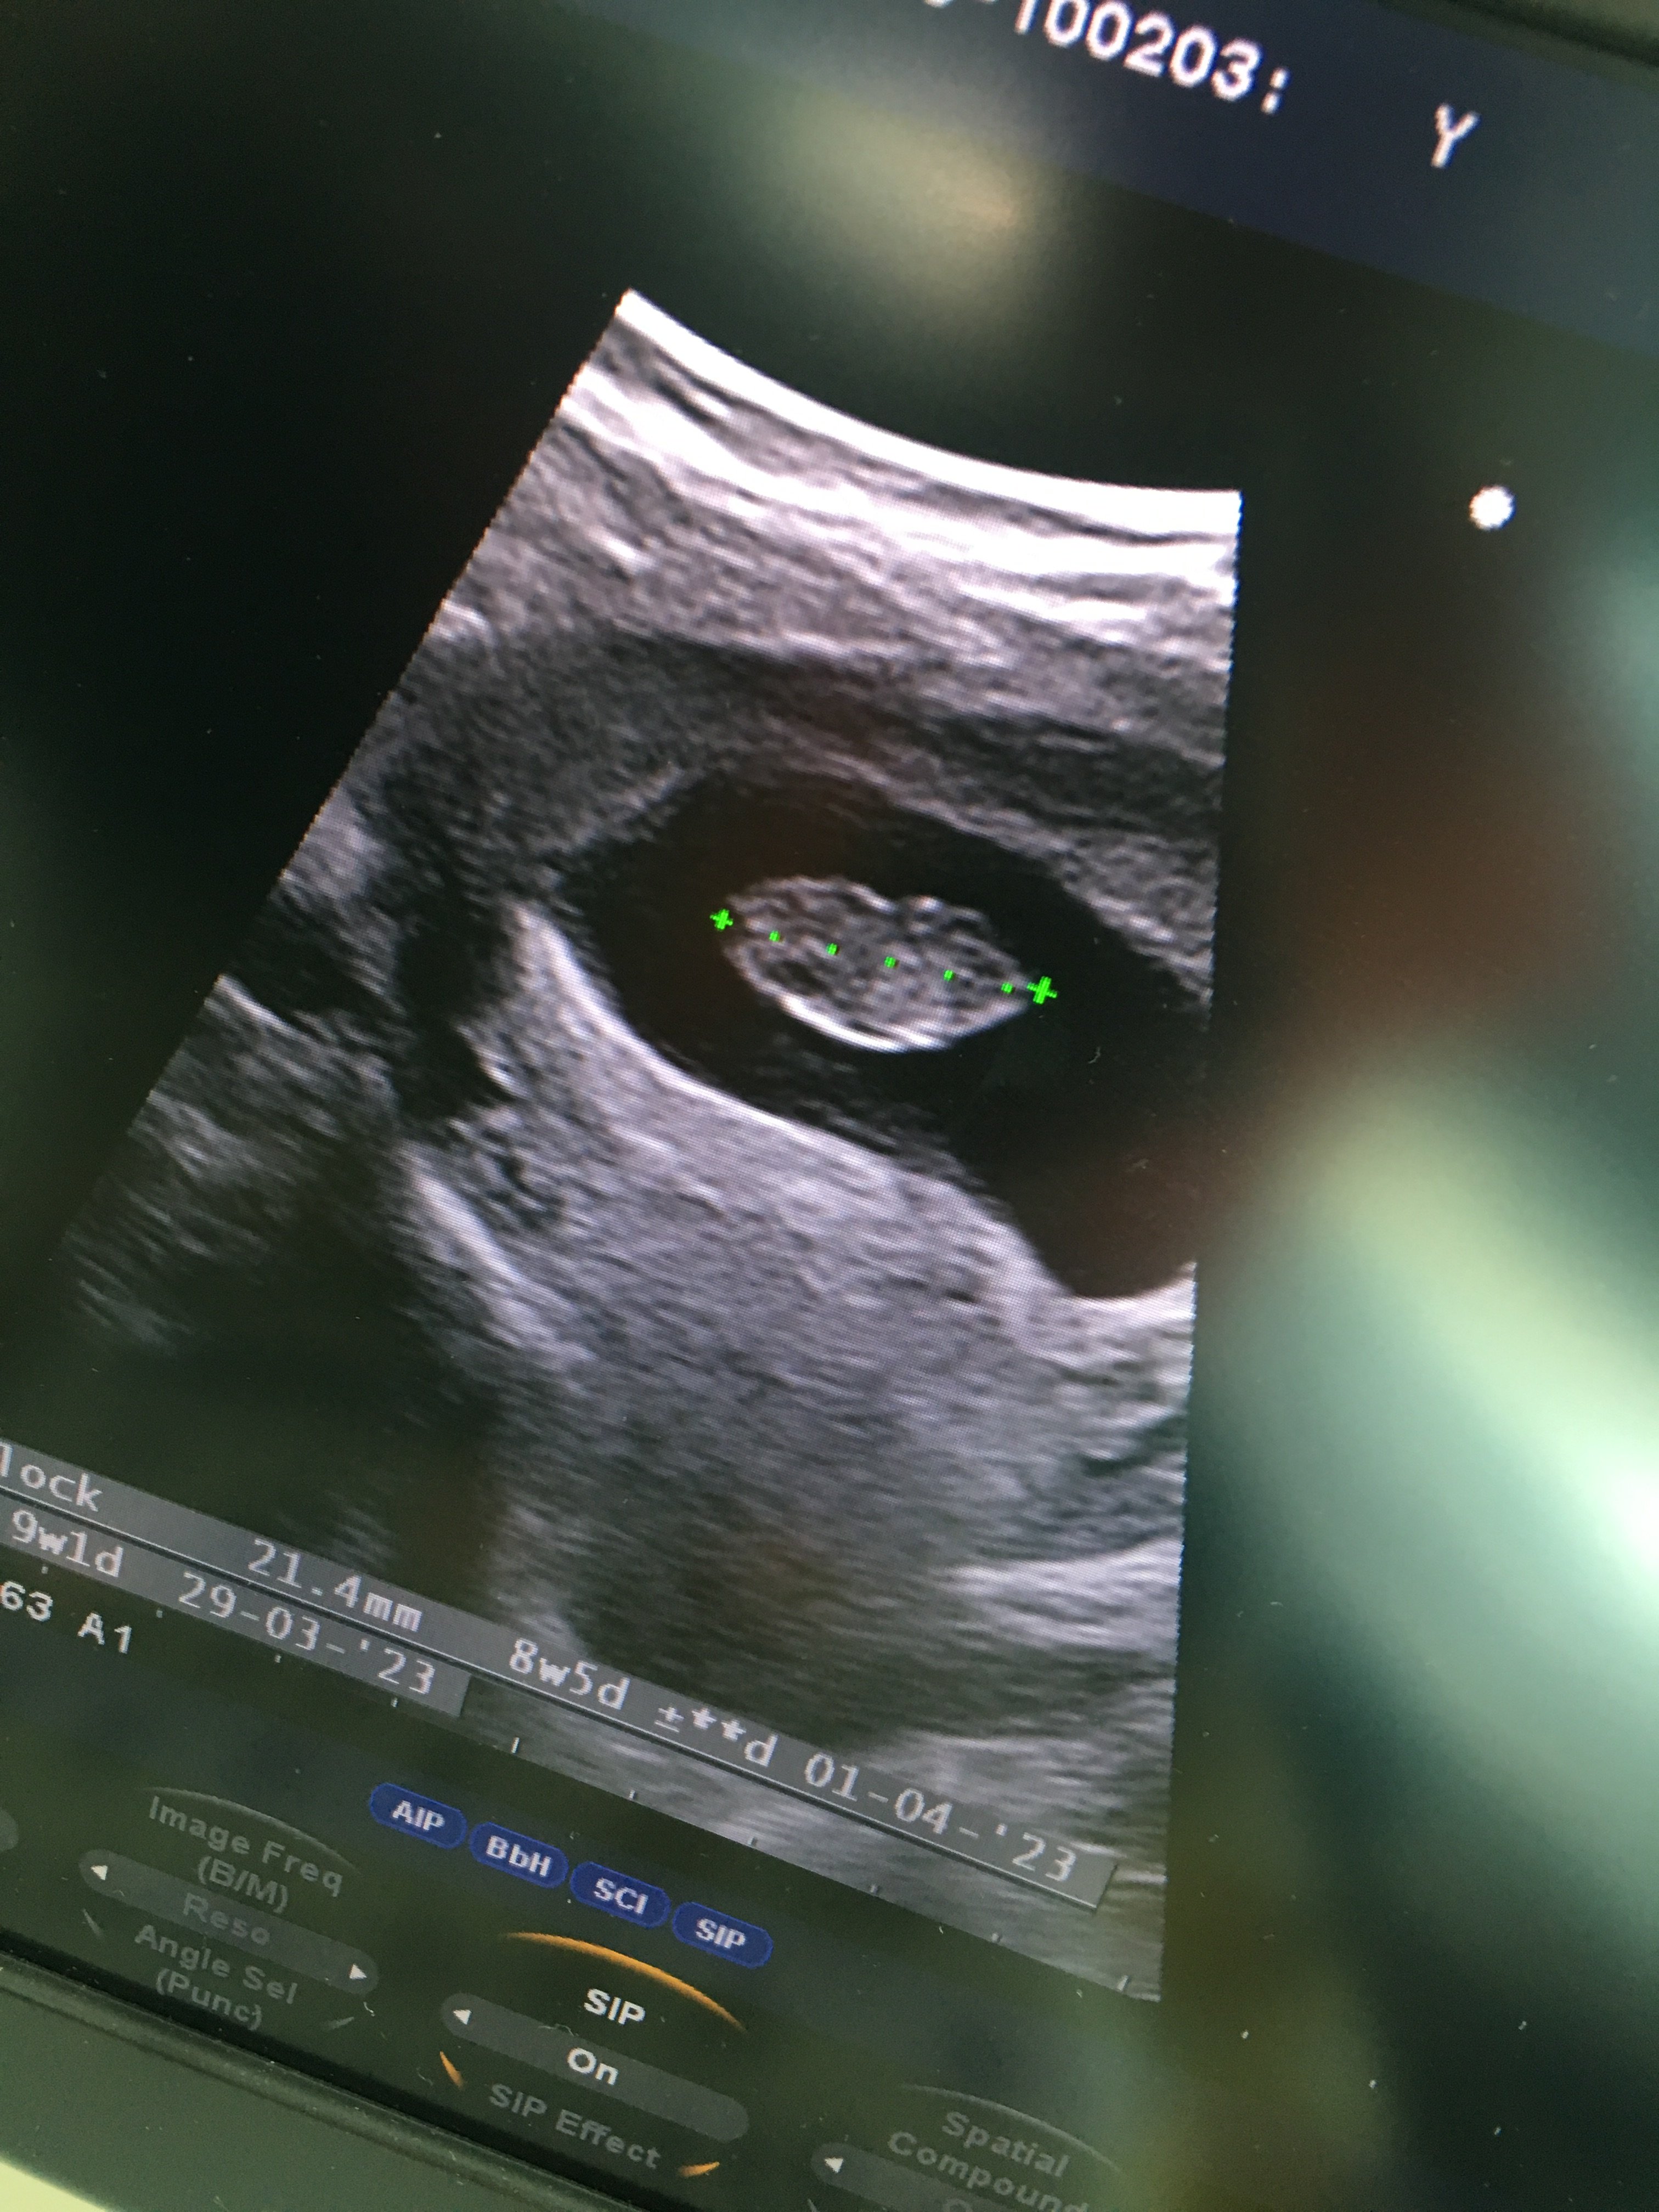

Merhaba kontrolden yeni geldim yeni ultrason görüntüsü atsam bakarmısınız acaba 8 hafta 5 günlük

Ekli dosyalar

• C322ECEE-B184-4942-8381-CF125DB8A380.jpeg

C322ECEE-B184-4942-8381-CF125DB8A380.jpeg

1,6 MB · Görüntüleme: 183